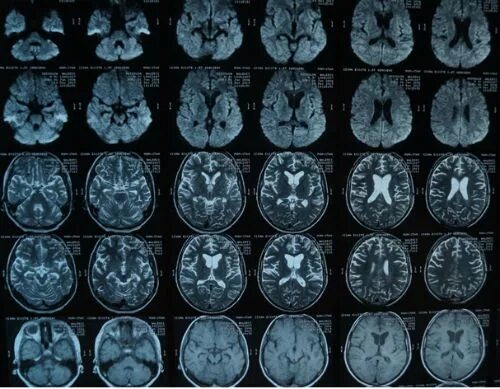

Мрт симптомы